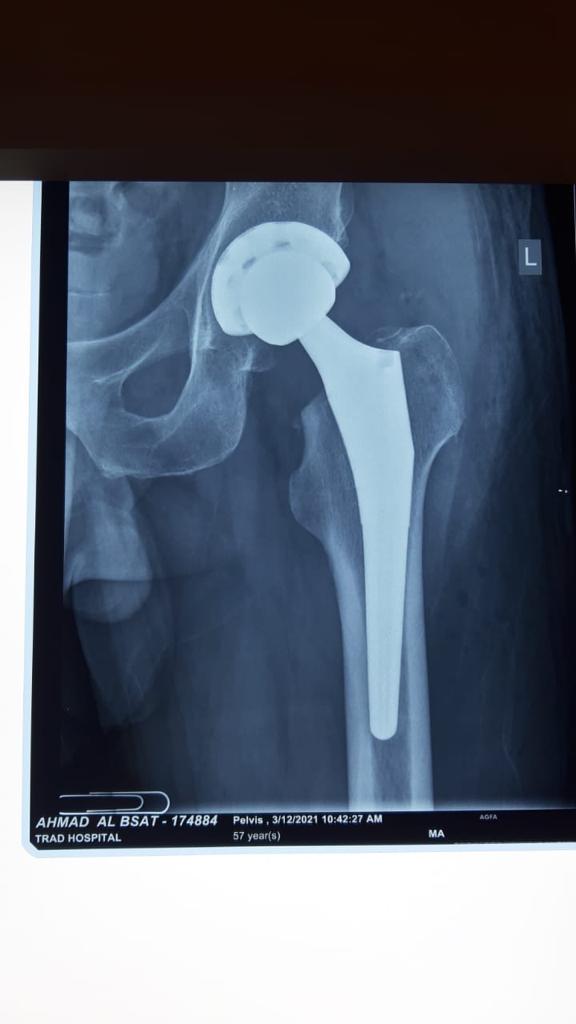

Total Hip Arthroplasty Anterior Approach